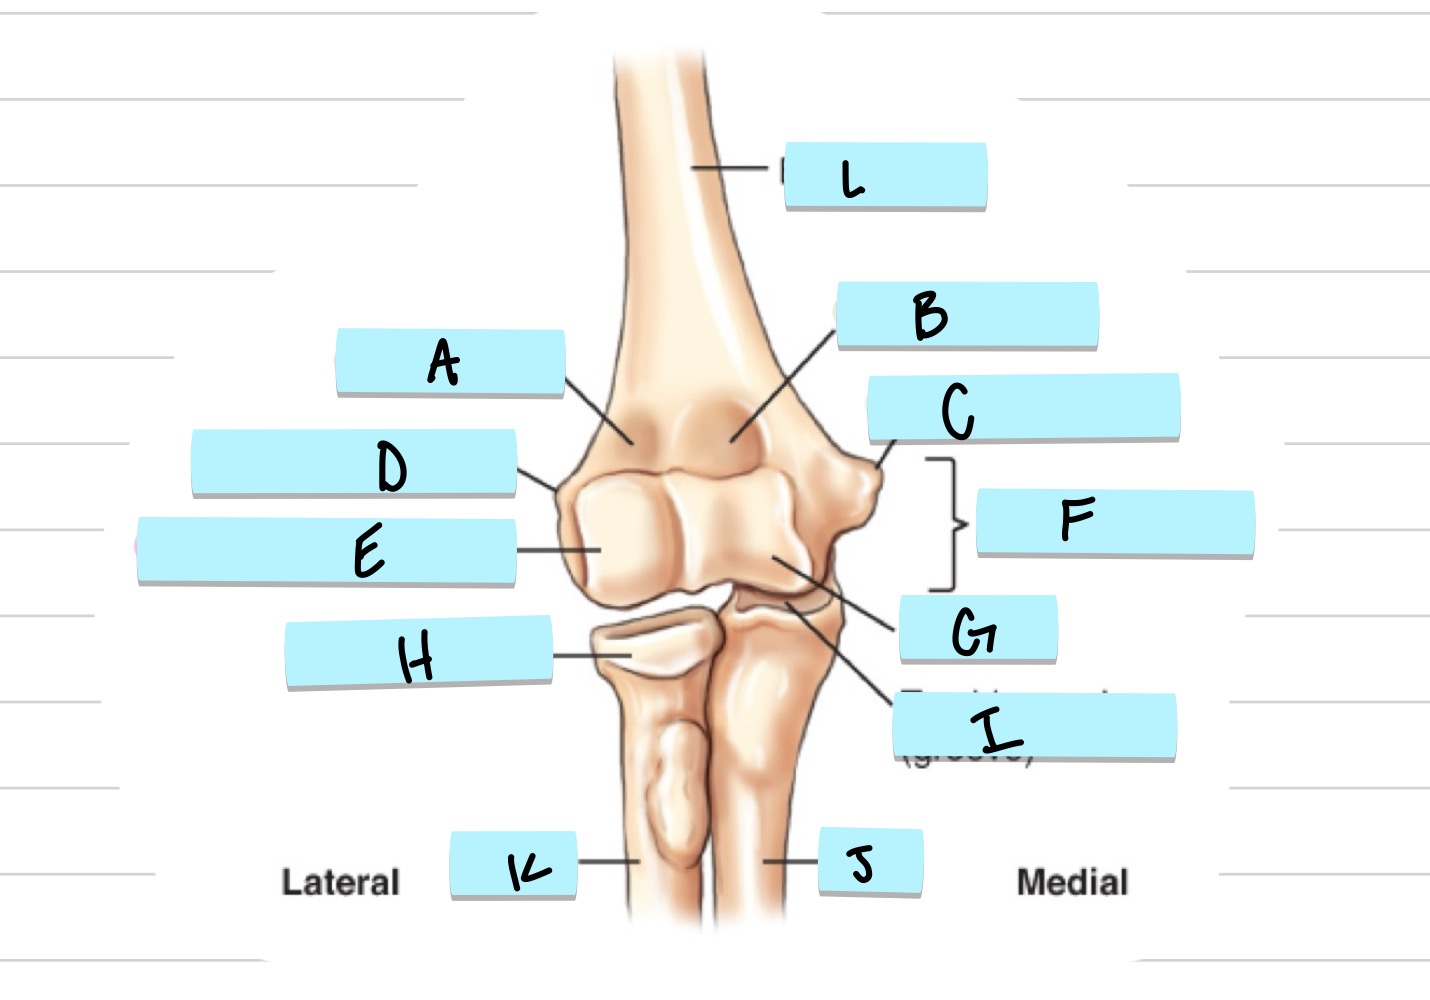

<p>What is A?</p>

What is A?

olecranon process

36

New cards

<p>what is B?</p>

what is B?

trochlear notch

37

<p>what is C?</p>

what is C?

coronoid process

38

<p>what is D?</p>

what is D?

radial notch

radial fossa

83

coronoid fossa

84